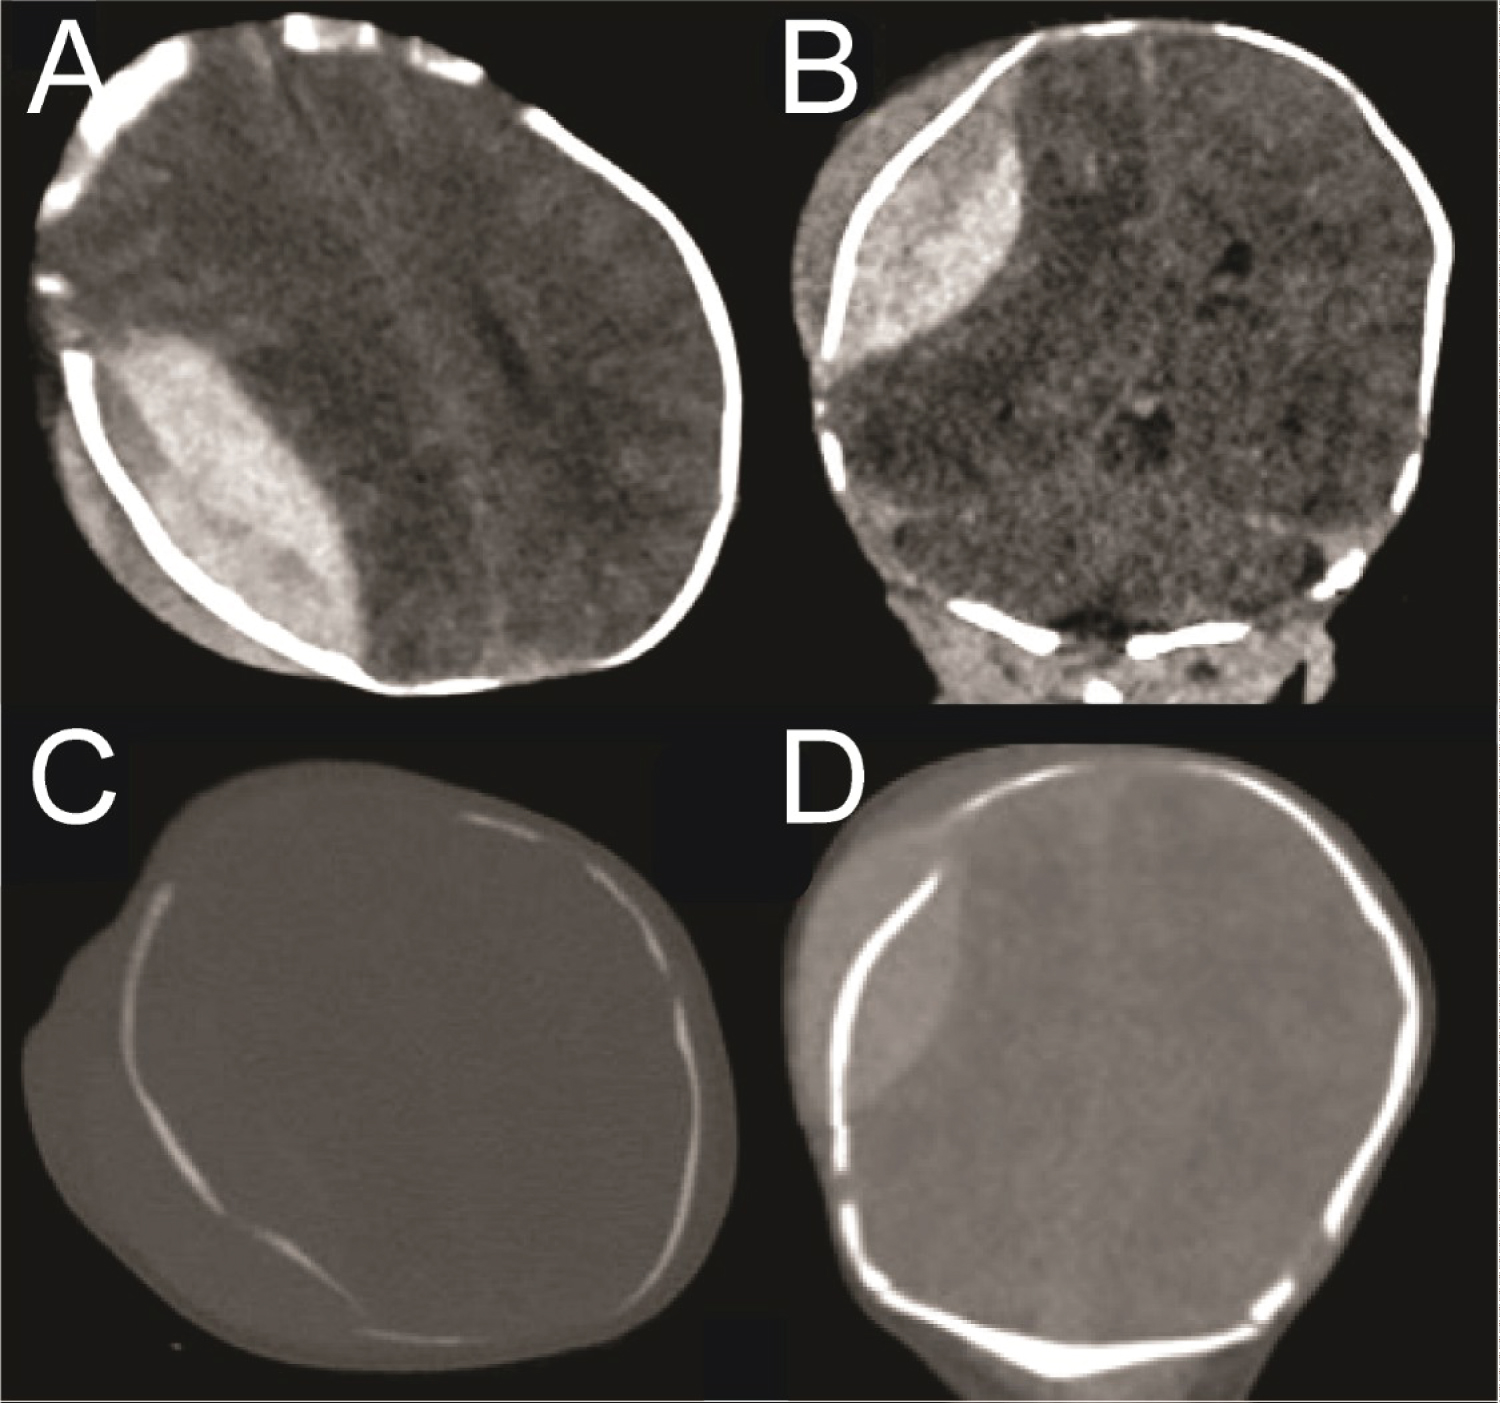

An initial head ultrasound (Figure 1) suggested the possibility of an epidural or subdural hematoma. Subsequent brain CT scans (Figure 2) revealed a large right-sided parietal EDH with a maximum thickness of 1.8 cm, diffuse subarachnoid blood, effacement of the right lateral ventricle, and a 4 mm midline shift. A CT scan of the bony window (Figure 2) uncovered a complex right parietal skull fracture with a 3 mm inwardly displaced depression of the fracture.

Figure 2: CT head with parietal EDH and skull fractures. (A) Axial view in the brain window demonstrating large EDH and overlying cephalohematoma; (B) Coronal view brain window showing the EDH; (C) Bony window of panel A; (D) Bony window of panel B. View Figure 2